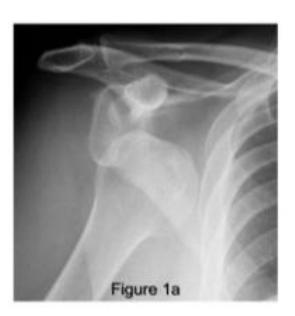

Anterior Shoulder Dislocation

What is the diagnosis shown in the image?

- Anterior Shoulder Dislocation

What is the most common complication of anterior shoulder dislocation?

- Axillary nerve injury

What is the associated injury in anterior shoulder dislocation?

- Lesser tuberosity fracture

18-year-old male presented after sport injury and unable to internally rotate his left shoulder. What is the likely finding?